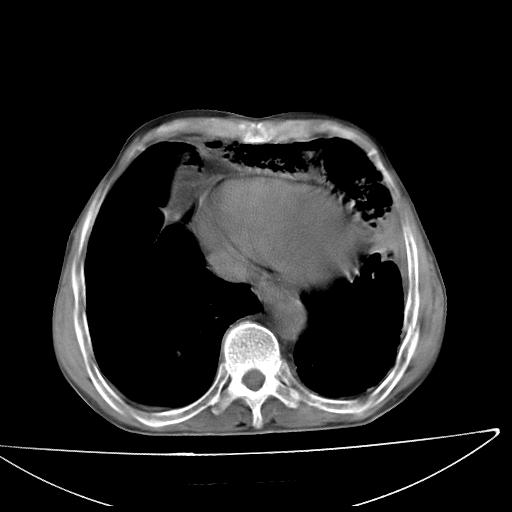

男  70岁,发烧咳嗽4天。盗汗,消瘦。无痰中带血丝,以前有肺tb病史,ct见,双肺tb,左侧胸廓塌陷,左胸膜肥厚粘连。纵隔移位,右侧胸腔积液,大家说说那个心影前左肺舌叶除了肺大炮还有炎症还是干酪性肺炎?有占位吗?我看纵隔淋巴结也大。

1)两肺继发性肺结核并左肺上叶肺不张,支气管扩张。2)双侧胸膜炎(胸膜增厚+少量胸腔积液)。

两肺继发性肺结核并感染,左肺上叶肺不张。建议ct增强。